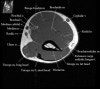

1. Coronal section

1) Collateral ligament

2) Common extensor/flexor tendon group patholgy as well as epicondylitis